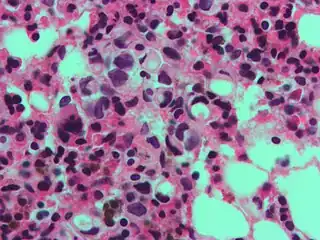

The name of the cell comes from its appearance; signet ring cells resemble signet rings. They contain a large amount of mucin, which pushes the nucleus to the cell periphery. The pool of mucin in a signet ring cell mimics the appearance of a finger hole and the nucleus mimics the appearance of the face of the ring in profile.

High magnification micrograph showing signet ring cells, with clear cytoplasm, in metastatic breast carcinoma. H&E stain.